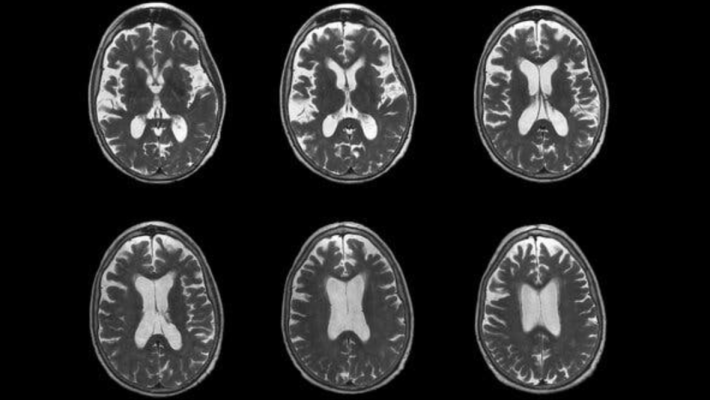

Foto d'archivio

La Food and Drug Administration americana autorizza l’atteso farmaco per l’Alzheimer di Eisai e Biogen. Negli studi eseguiti il Leqembi ha mostrato risultati promettenti per la cura della malattia, da cui sono affetti circa 6,5 milioni di americani, con un evidente rallentamento della malattia.